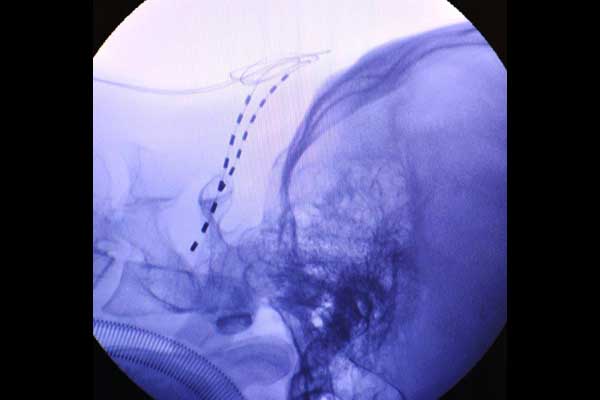

Wirkmechanismen von Botulinumtoxin A (Botox) in der Pathophysiologie der Migräne Gesamtübersich

Das Medikament Botox® (Botulinumtoxin Typ A) hat am 23. September 2011 die Zulassung zur Linderung der Symptome von chronischer Migräne bei Erwachsenen, die unzureichend auf prophylaktische Migränebehandlungen angesprochen haben oder diese nicht vertrugen, vom Bundesinstitut für Arzneimittel und Medizinprodukte (BfArM) erhalten. Die Zulassung erfolgte auf Basis des sogenannten Verfahrens der gegenseitigen Anerkennung (Mutual Recognition Procedure) in 14 europäischen Ländern.

Nachdem in Kasuistiken die Wirkung von Botulinumtoxin Typ A bei Migräne beschrieben wurde, erfolgte zunächst der vergebliche Versuch eines Wirkungsnachweises bei der häufigeren episodischen Migräne. Erst durch das PREEMPT-Studienprogramm mit Botox® in der Behandlung der chronischen Migräne konnte ein Wirknachweis für diese schwer betroffene Subpopulation erbracht werden. Damit steht erstmals eine wirksame und verträgliche Behandlungsoption zur Prophylaxe der chronischen Migräne zur Verfügung, die jedoch in ein therapeutisches Gesamtkonzept eingebunden werden muss. Die Erstzulassung von Botox® für die Indikation „Vorbeugung von Kopfschmerzen bei Erwachsenen mit chronischer Migräne (≥15 Kopfschmerztage, ≥ 8 Tage mit Migräne pro Monat) erfolgte im Jahre 2010 in England und den USA. Botox hat am 23. September 2011 die Zulassung zur Linderung der Symptome von chronischer Migräne bei Erwachsenen, die unzureichend auf prophylaktische Migränebehandlungen angesprochen haben oder diese nicht vertrugen, vom Bundesinstitut für Arzneimittel und Medizinprodukte (BfArM) erhalten. Die Zulassung erfolgte auf Basis des sogenannten Verfahrens der gegenseitigen Anerkennung (Mutual Recognition Procedure) in 14 europäischen Ländern. Die Behandlung der chronischen Migräne (15 Kopfschmerztage im Monat, von denen 8 Kopfschmerztage eindeutig Migräne sein müssen) mit Botox wird auch von den gesetzlichen Kassen übernommen.